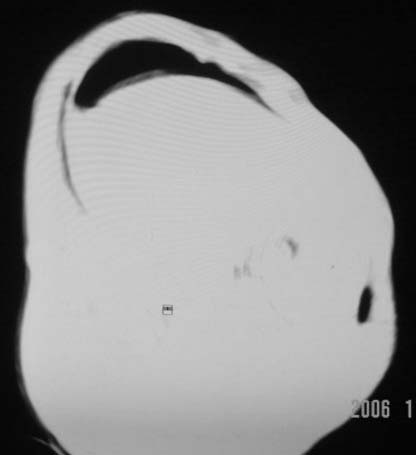

仰卧位见:肝前间隙及肝脾间隙内可见新月形气体密度影,边缘清楚,侧卧位见气体随体位改变而移动,ct值约-929hu。膈下、肝下间隙及部分肠间隙可见液性密度影。考虑:1、上腹部空腔脏器穿孔,以胃穿孔可能性大。2、少量腹水。

仰卧位见:肝前间隙及肝脾间隙内可见新月形气体密度影,边缘清楚,侧卧位见气体随体位改变而移动,ct值约-929hu。膈下、肝下间隙及部分肠间隙可见液性密度影。考虑:1、上腹部空腔脏器穿孔,结合临床,首先考虑胃穿孔可能性大。2、少量腹水

支持消化道空腔脏器穿孔(腹腔内大量游离气体影,小网膜囊内亦见气体影),少量腹水。